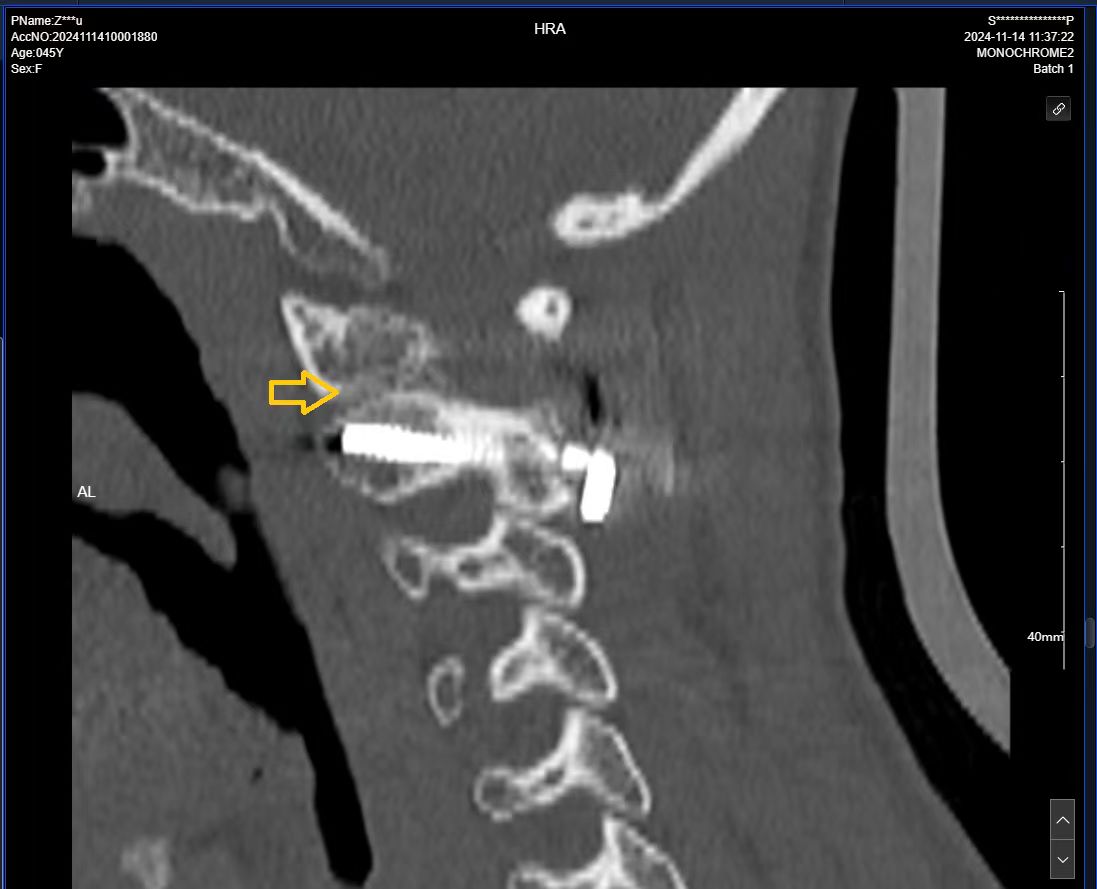

• 术后影像:

• 2024.11.07,复查,对位良好。